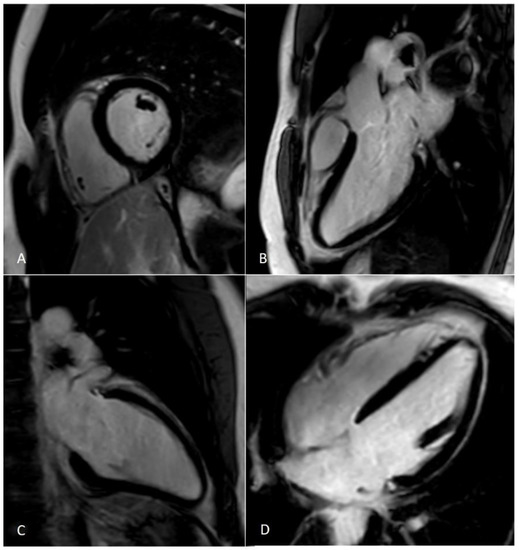

Figure 8.

Assessment of myocardial scar with semiautomatic tissue characterization. Semiautomatic tissue characterization algorithm allowing the identification of myocardial scars (represented by hyper-enhanced myocardium in panel (A) and yellow-colored myocardium in panel (B)) by positioning a region of interest within the territory of the remote/normal myocardium (dark myocardium). Green: epicardial contour; red: endocardial contour; yellow: myocardial scar; blue: normal myocardium.